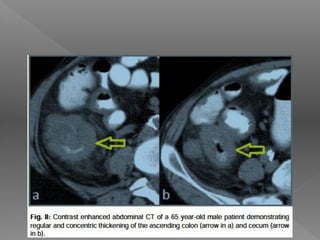

 CT Abdomen

Investigations  CT Abdomen Better than USG for detecting  High density ascites  Lymphadenopathy with caseation  Bowel wall thickening  Irregular soft tissue densities in omental area  Tuberculosis of liver & spleen